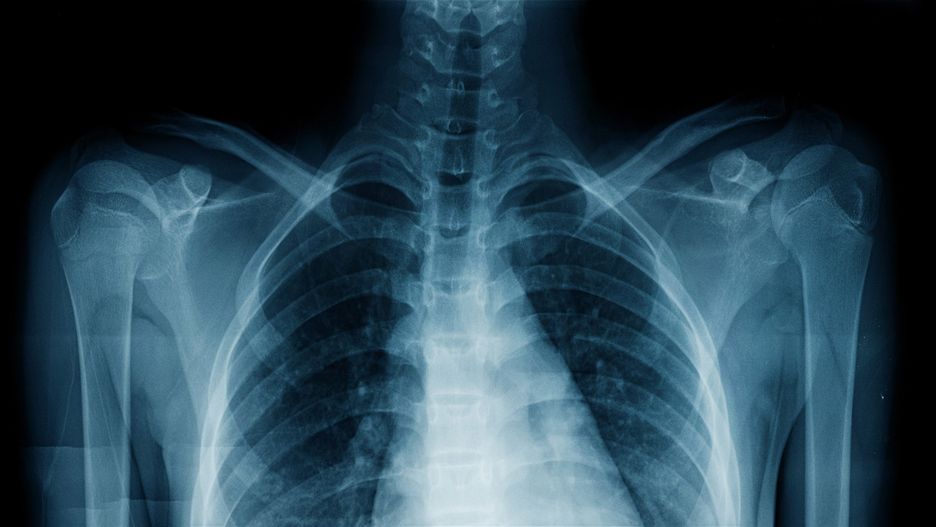

Naukowcy odkryli, że SI może być w stanie zidentyfikować rasę człowieka na podstawie samych zdjęć rentgenowskich i tomograficznych z około 90-procentową dokładnością. Ich badania zostały opublikowane w czasopiśmie Lancet Digital Health.

W celu sprawdzenia zdolności sztucznej inteligencji do rozpoznawania obrazów, modelowi głębokiego uczenia podano najpierw zdjęcia tomograficzne i rentgenowskie wielu różnych obszarów ciała odrębnych grup ludzi. Z obrazów usunięto etykiety wraz z wszelkimi możliwymi cechami identyfikacyjnymi, takimi jak kolor skóry i włosów, po czym poproszono SI o zidentyfikowanie rasy danej osoby. W przypadku wszystkich obszarów ciała SI była w stanie zidentyfikować rasę z około 90-procentową dokładnością, nawet bez żadnych cech identyfikacyjnych.

Mając na uwadze wszystkie podstawy, badacze zastanawiali się, czy SI nie działała podstępnie, wykorzystując statystyki do odgadywania na podstawie zmiennych, takich jak wskaźnik masy ciała (BMI) lub gęstość piersi, które mogłyby sugerować, że dana rasa jest inna. Naukowcy usunęli możliwe zmienne i pokazali SI tylko zestawy danych osób o podobnym BMI i typie ciała, ale mimo to maszyna była w stanie zidentyfikować rasę.

Naukowcy wysunęli hipotezę, że SI potrafi rozpoznać różnice w zawartości melaniny w skórze białych i czarnych osób, które mogą być widoczne na skanach tomograficznych i rentgenowskich, ale pozostawać niezauważalnymi dla ludzi. Zanim jednak SI będzie mogła być wykorzystywana w szpitalach, badacze będą musieli przeprowadzić dodatkowe obserwacje. "Nie możemy spieszyć się z wprowadzaniem algorytmów do szpitali i klinik, dopóki nie będziemy pewni, że nie podejmują one decyzji rasistowskich czy seksistowskich" – powiedział Leo Anthony Celi, współautor i profesor nadzwyczajny w Harvard Medical School.